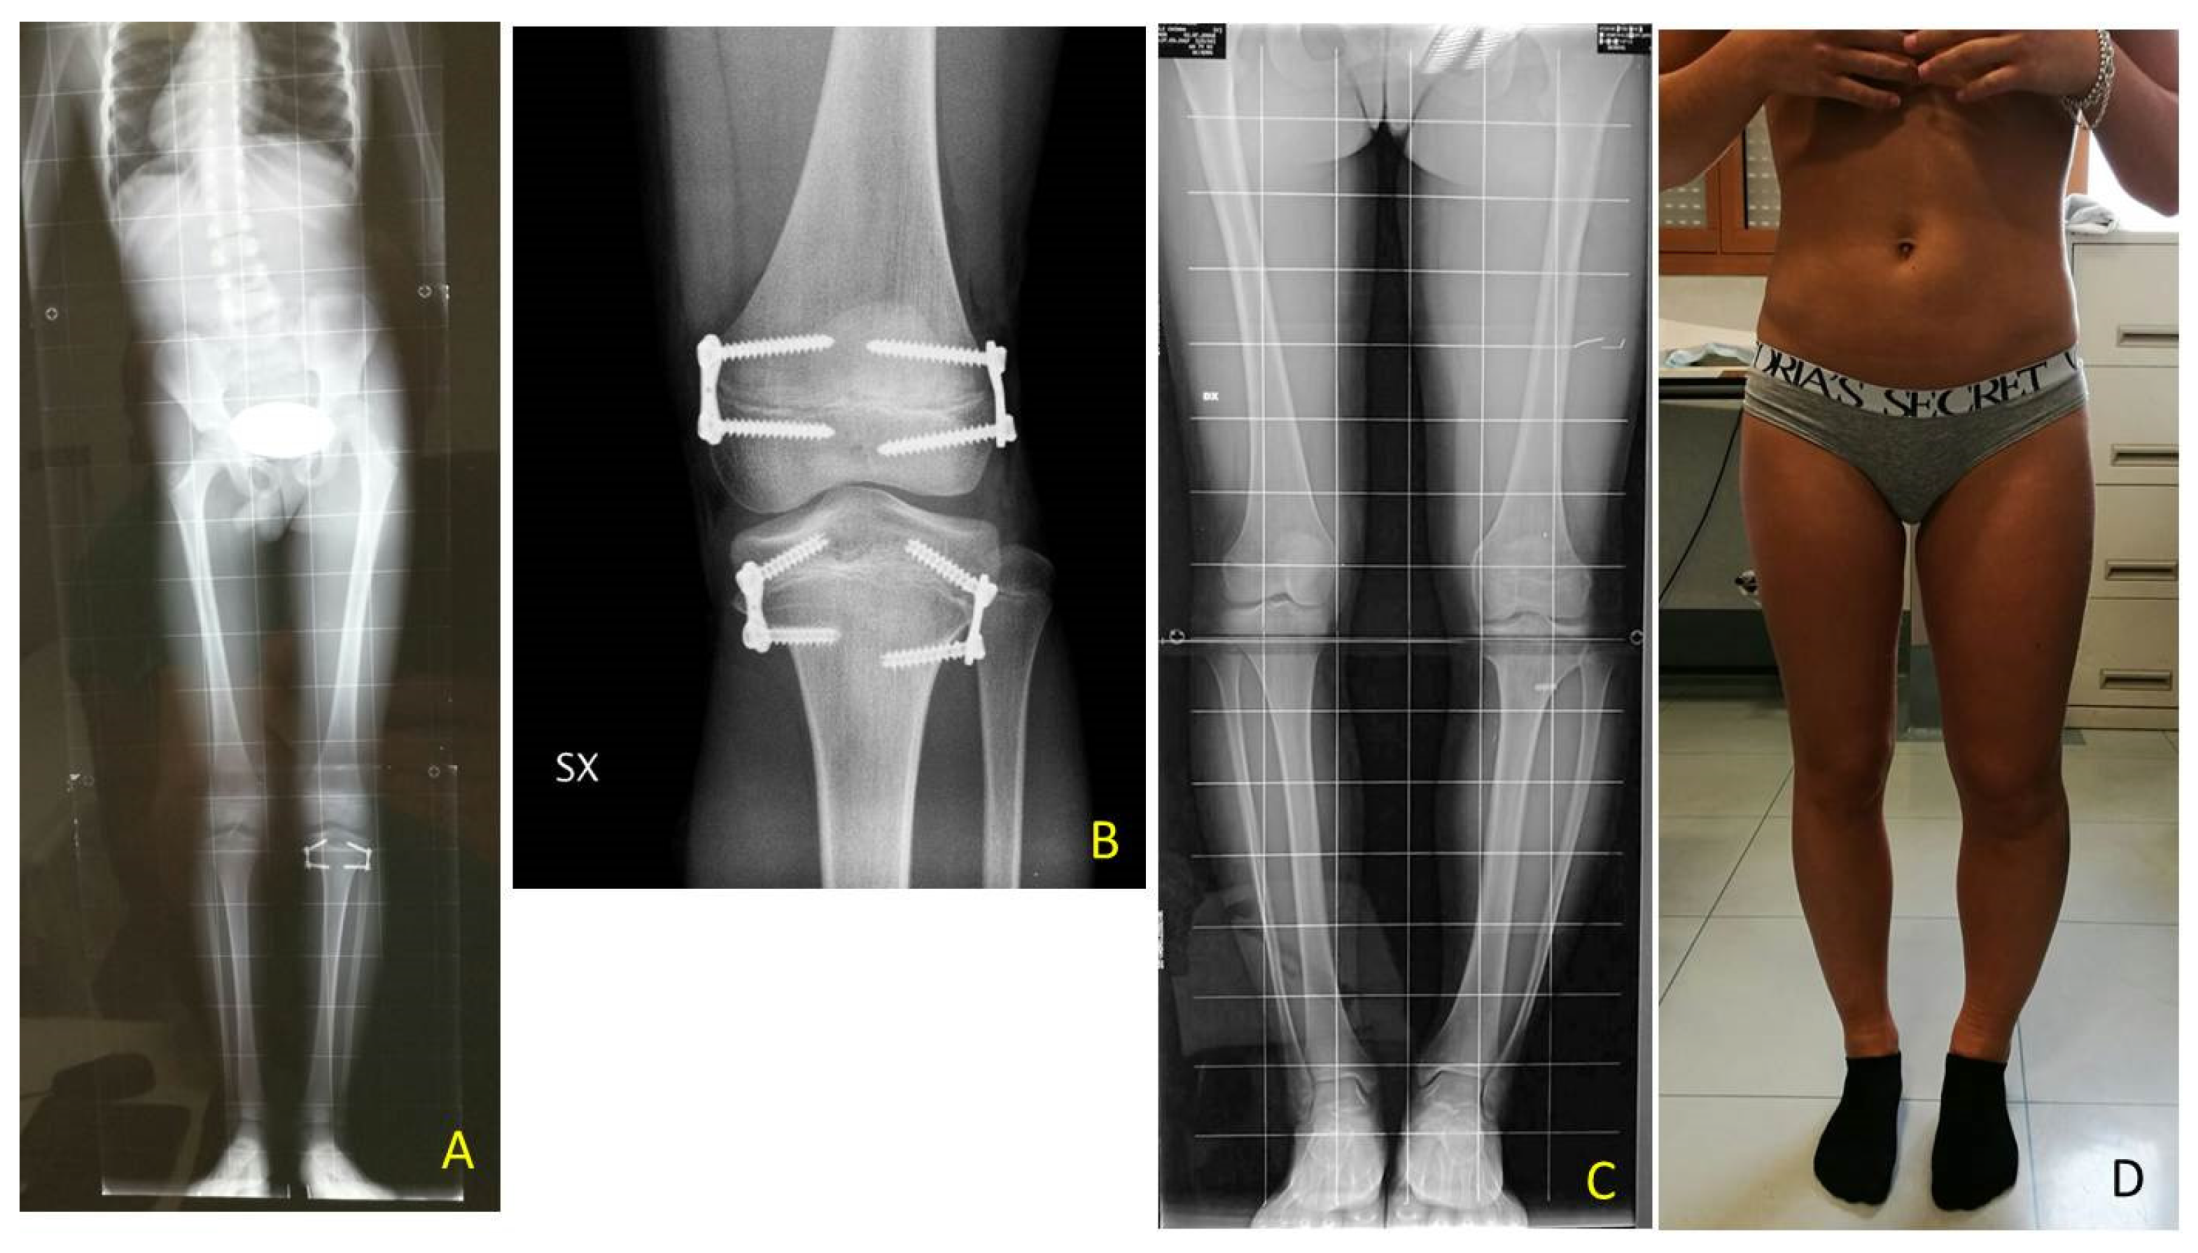

Temporary epiphysiodesis’s main complications were: 14 implant migrations with secondary varus-valgus axial deviation in a total of 6 patients. Hemi-epiphysiodesis was necessary to correct axial deviation that occurred during growth. To have a greater effectiveness in growth plate block, new bigger “quad” plates were used (8) in 6 cases. In only two cases screw breakage occurred during surgical removal (Figure 10).

Figure 10. BWS (Beckwith-Wiedemann syndrome) female patient with severe LLD (leg length discrepancy) left. At age of 7 years with a length discrepancy of femur of 1.5 cm and of 3.5 cm of tibia a PTE (temporary proximal tibia epiphysiodesis) was performed: (A) at age of 9.4 years femur discrepancy of 3.0 cm was present leading to a severe pelvis obliquity without shoe lift correction as shown in X-ray od spine and lower extremities; (B) postoperative X-ray in antero-posterior projection showing performed DFE (temporary distal femur epiphysiodesis); (C) at age of 12.7 years, after reaching leg length equality, removal of implants was performed. X-ray showing screw breakage on lateral aspect of tibia; (D) clinical aspect at follow-up with mild varus knee deformity bilaterally and nonpelvic obliquity.